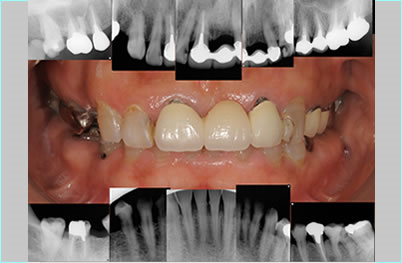

納得のインフォームド・コンセント、手術内容を患者様に説明して納得していただき、確信を持った完璧に近い手術をします。